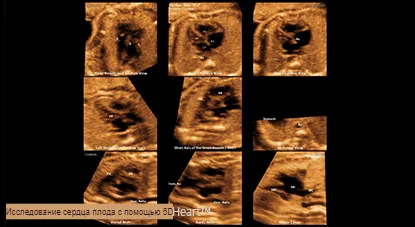

5D HeartTM Функция обеспечивает 9 стандартных плоскостей сердца, используя данные STIC плода, а также важную информацию о развитии сердца плода простым и точным способом в соответствии с рекомендациями AIUM.